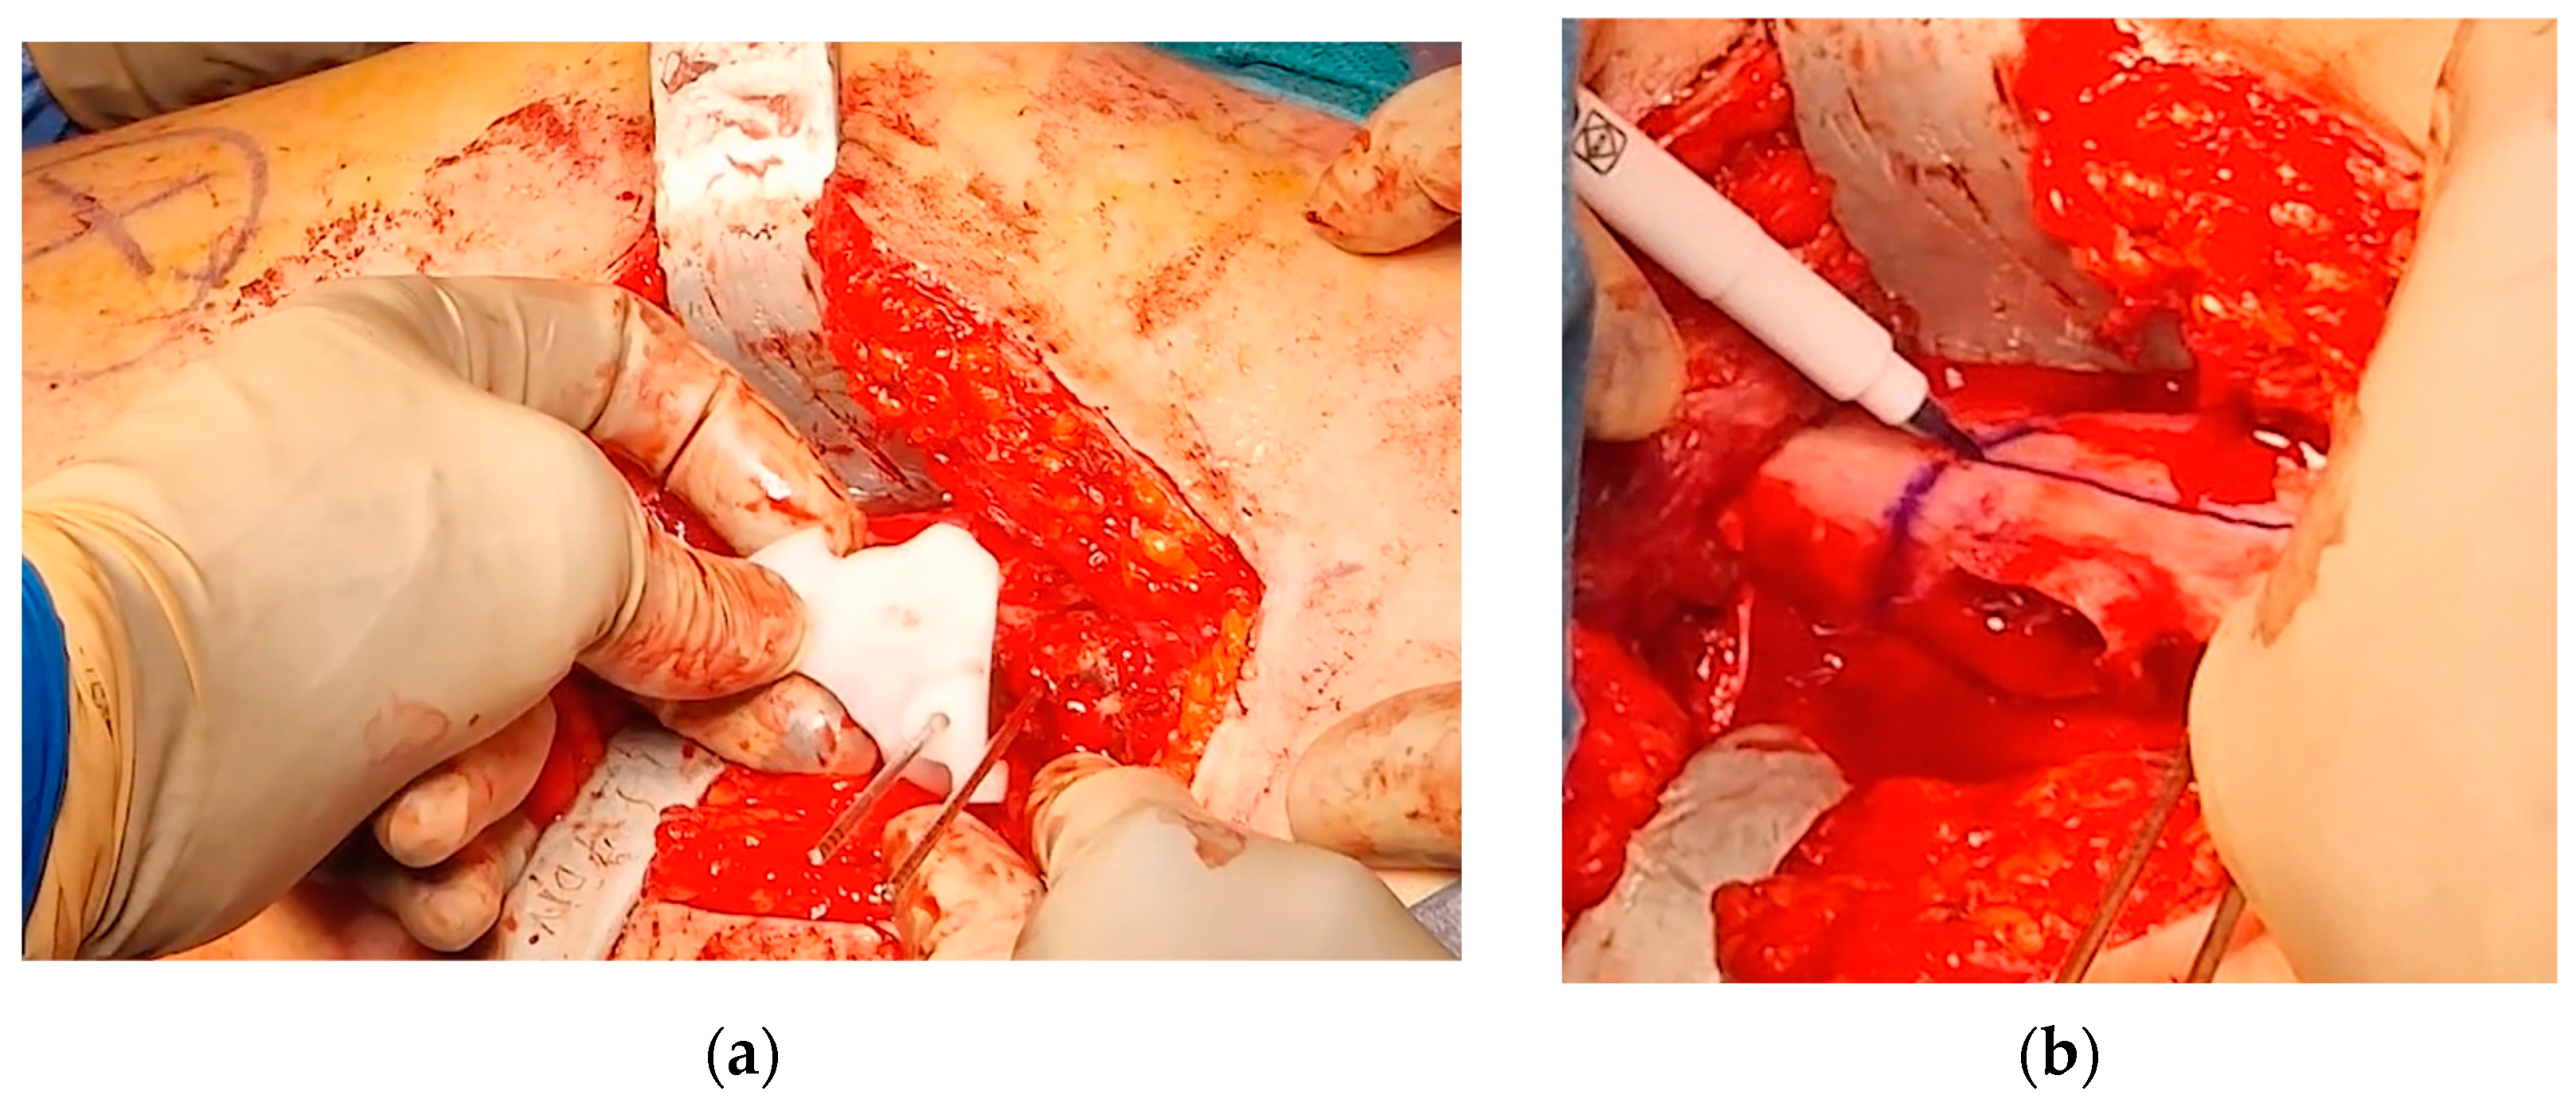

2.2. Surgical Procedure